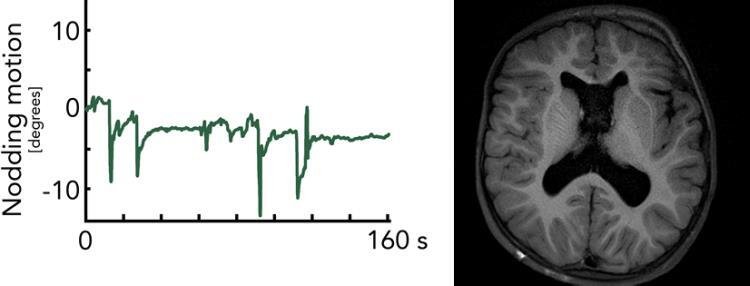

Motion monitoring of one of our pediatric patients being examined with our motion robust real-time corrected MR protocol based solely on our own pulse sequences. Above is a 3D rendering of the child's face as seen by the point cloud camera. Below is motion information for the entire MRI scan, which is continuously fed back to the imaging process to make the image planes follow the head movements

Motion robust pulse sequences - Snapshot SWI-EPI

Despite real-time motion correction with Tracoline or WRAD, it is fundamentally difficult to obtain good image quality with long-TE 3D sequences such as SWI. Even with an ideal motion correction, the phase changes in the brain (which occur due to long echo times) result in image artifacts (top-right, 3D EPI). With our snapshot 2D SWI EPI, a complete image plane is obtained in 0.1 s under the same phase conditions in the brain. Several repetitions of the same image plane are averaged after motion correction to increase the SNR to the appropriate level.